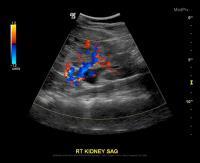

1.     ممکن است سونوگرافی شکم یا لگن انجام شود. سونوگرافی یک روش تصویربرداری است که از امواج صوتی برای ایجاد تصاویری از داخل شکم و یا لگن استفاده می‌کند.

سونوگرافی یا اولترا سوند، یک روش تشخیصی است که از اواج با فرکانس بالا برای تولید تصاویری از ساختارهای درونی بدن استفاده می‌شود. این تصاویر می‌توانند اطلاعات ارزشمندی را برای تشخیص و درمان انواع بیماری‌ها و شرایط ارائه دهند. سونوگرافی تشخیصی یک روش بی خطر است که از امواج صوتی کم توان استفاده می‌کند و هیچ خطر شناخته شده‌ای برای بدن ندارد.

سونوگرافی ابزار ارزشمندی است، اما محدودیت‌هایی دارد. در این روش، صدا به خوبی از طریق هوا یا استخوان عبور نمی‌کند، بنابراین سونوگرافی در تصویربرداری از قسمت‌هایی از بدن که دارای گاز هستند یا توسط استخوان پنهان شده اند، مانند ریه‌ها یا سر، نمی‌تواند موثر باشد.

یک تکنسین آموزش دیده (سونوگرافیست) یک دستگاه کوچک و دستی (ترانسدیوسر) را روی ناحیه مورد مطالعه فشار می‌دهد و آن را در صورت نیاز حرکت می‌دهد تا تصاویر را ثبت کند. مبدل امواج صوتی را به بدن شما می‌فرستد و امواجی را که باز می‌گردند جمع آوری می‌کند و آنها را به کامپیوتر می‌فرستد و در نهایت، تصاویر را ایجاد می‌کند.

در سونوگرافی، می‌توان بدون استفاده از اشعه‌های یونیزان خطرناک، شرایط بیماران کم سن و جوان بررسی شود. این روش در صورتی که در یک مرکز معتبر و یک تکنسین مجرب انجام می‌شود، می‌تواند به صورت دقیق و قابل اعتماد، شرایط آپاندیس را نشان دهد.

سونوگرافی معمولا بدون درد است. با این حال، هنگامی که سونوگرافیست مبدل را بر روی بدن شما هدایت می‌کند، ممکن است ناراحتی خفیفی را تجربه کنید. معاینه سونوگرافی معمولا از 30 دقیقه تا یک ساعت طول می‌کشد.